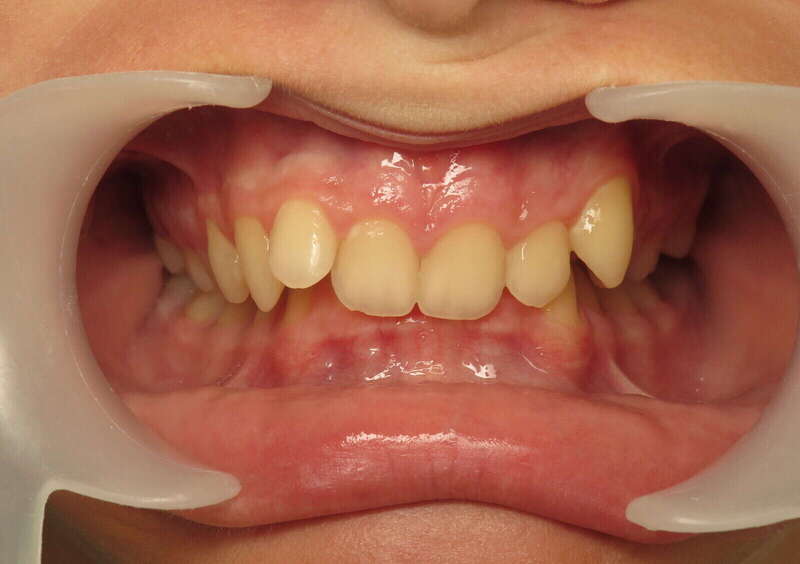

Cas n°2 traité par aligneurs - adolescent

Ce cas d'une adolescente illustre la puissance des aligneurs dans la correction d'une Classe II sévère sans extraction. La stratégie a reposé sur une distalisation séquentielle de l'arcade supérieure, soutenue par une coopération soutenue du port d'élastiques intermaxillaires.

Cette approche a permis d'annuler un surplomb incisif (overjet) important tout en réhabilitant une occlusion de Classe I stable. L'absence d'extraction a été déterminante pour préserver l'harmonie du profil, évitant le creusement du visage souvent lié aux traitements soustractifs classiques.

• Conservation dentaire : Alignement total sans perte de prémolaires.

• Fonctionnalité : Engrènement parfait et stable.

• Esthétique faciale : Soutien labial optimal et sourire élargi.

C'est une démonstration claire de l'orthodontie moderne : efficace, esthétique et respectueuse de l'anatomie naturelle.